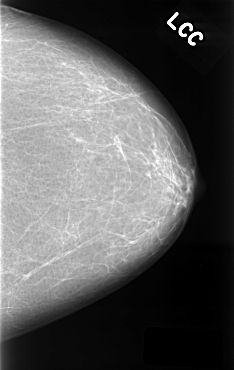

C_0319_1.LEFT_CC

LEFT_CC LINES 4440 PIXELS_PER_LINE 2800 BITS_PER_PIXEL 12 RESOLUTION 50 NON_OVERLAY